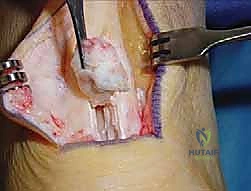

3. استئصال الأنسجة التالفة (Debridement)

هذه خطوة حاسمة. يتم فتح الغلاف المحيط بوتر أخيل وفحص الوتر بدقة. يقوم الجراح بإزالة جميع الأنسجة الندبية، الميتة، والمتكلسة (التي تسبب الألم). في الحالات الشديدة، قد يتم إزالة أكثر من 50% من حجم وتر أخيل الأصلي لأنه لم يعد صالحاً للعمل.

4. عزل وحصاد وتر FHL (Tendon Harvesting)

يتم تحديد مسار وتر FHL الذي يقع أعمق قليلاً من وتر أخيل. يتم فصل الوتر بعناية من نقطة اتصاله السفلية (عند منتصف القدم تقريباً) لضمان الحصول على طول كافٍ للنقل. وتجدر الإشارة هنا إلى أن قطع هذا الوتر لا يؤثر بشكل ملحوظ على وظيفة المشي أو حركة إصبع القدم الكبير، حيث تتولى عضلات أخرى هذه المهمة بكفاءة.

5. نقل وتثبيت الوتر (Tenodesis & Fixation)

هنا يتجلى الفن الجراحي. يتم حفر نفق صغير جداً في عظم الكعب (Calcaneus). يُسحب وتر FHL القوي ويُزرع داخل هذا النفق العظمي. يتم تثبيته باستخدام مسمار تداخلي حيوي (Bio-interference screw) يندمج مع العظم بمرور الوقت، مما يوفر تثبيتاً صخرياً قوياً.

بالإضافة إلى ذلك، يقوم الدكتور هطيف بخياطة ما تبقى من وتر FHL مع وتر أخيل الأصلي (Side-to-side anastomosis) لتعزيز القوة الميكانيكية المزدوجة.